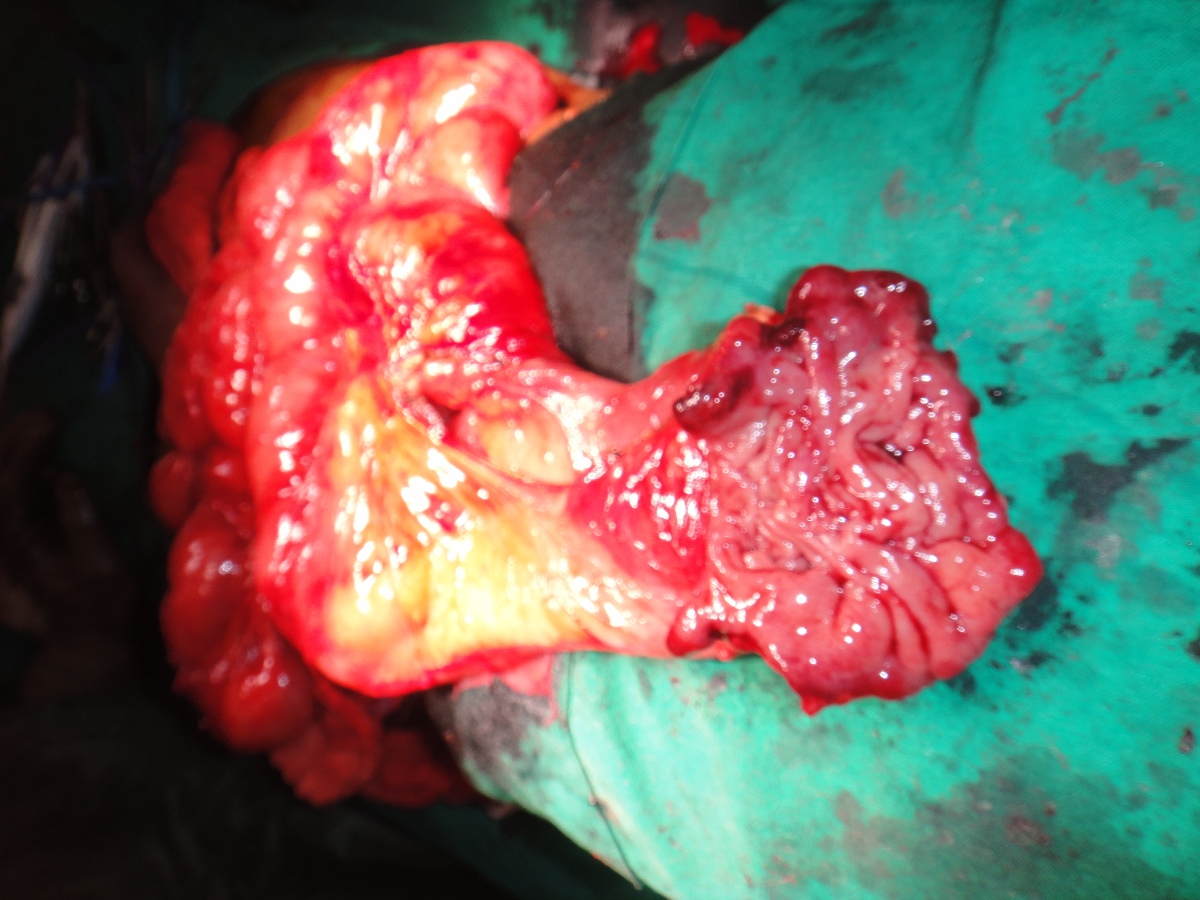

62 yrs old male having left buccal mucosa carcinoma with involvement of upper and lower GB sulcus.left radical neck dissection with left buccal mucosa growth excision with left hemi mandibulectomy with lower partial maxillectomy with left PM flape done